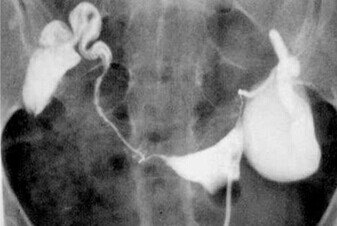

输卵管积水为慢性输卵管炎症中较为常见的类型,是指因流产、引产、不洁*交性**、盆腔感染等原因造成输卵管远端阻塞,使输卵管管壁扩张并形成积液的病理过程,是导致不孕症的重要原因。

关于输卵管积水对IVF妊娠结局的影响,研究结果显示,输卵管积水使IVF-ET 的着床率及妊娠率降低、流产率增加,主张先处理输卵管积水再进行IVF-ET,一般选择手术治疗。目前学术界对输卵管积水手术方式的选择意见不一,常用的手术方式有经阴道超声下输卵管积水抽吸术、输卵管切除术、输卵管伞端或壶腹部造口术、输卵管近端结扎术等,以及近年来开展的输卵管栓塞术等。

1、经阴道超声下输卵管积水抽吸术,其机制可能是降低了输卵管压力,防止积水流向宫腔,避免输卵管积水的液体对胚胎的毒性作用。但是此法易使输卵管积水复发,故有时需多次穿刺抽吸。

2、近年来,学术界提倡以切除积水严重的输卵管作为IVF-ET前的首选处理方式。Verhulst等在1994年报道切除积水的输卵管不会影响卵巢功能,且可能更易监测卵泡发育,其临床妊娠率明显高于术前。此后相似的报道不胜枚举。但也有大量研究认为,输卵管切除术可能会破坏同侧卵巢的血供,影响该侧卵巢激素的分泌以及卵泡发育,故输卵管切除术并非最佳方案。

3、一些研究者主张在输卵管积水不严重的情况下应尽量保留卵巢功能,可在腹腔镜或开腹手术下行输卵管伞端或壶腹部造口术,此术式保留了输卵管,避免影响同侧卵巢血供和卵泡发育,胚胎移植的妊娠率亦可提高,缺点是有可能出现异位妊娠,个别患者输卵管积水会复发。

4、输卵管近端结扎术 有研究称输卵管近端结扎术与输卵管切除术对卵巢血供的影响及对患者IVF结局的影响无显著差异性,而有学者提出输卵管近端结扎、远端造口手术和腹腔镜输卵管切除术并不减弱卵巢的超排卵反应,故可作为IVF-ET前处理输卵管积水的主要选择。

5、此外,最新的研究显示,输卵管栓塞术与其他传统4种术式比较具有简便、安全、经济的特点,不但不影响卵巢功能,还可显著增加临床妊娠率、杜绝输卵管妊娠的发生,具有良好的应用前景。